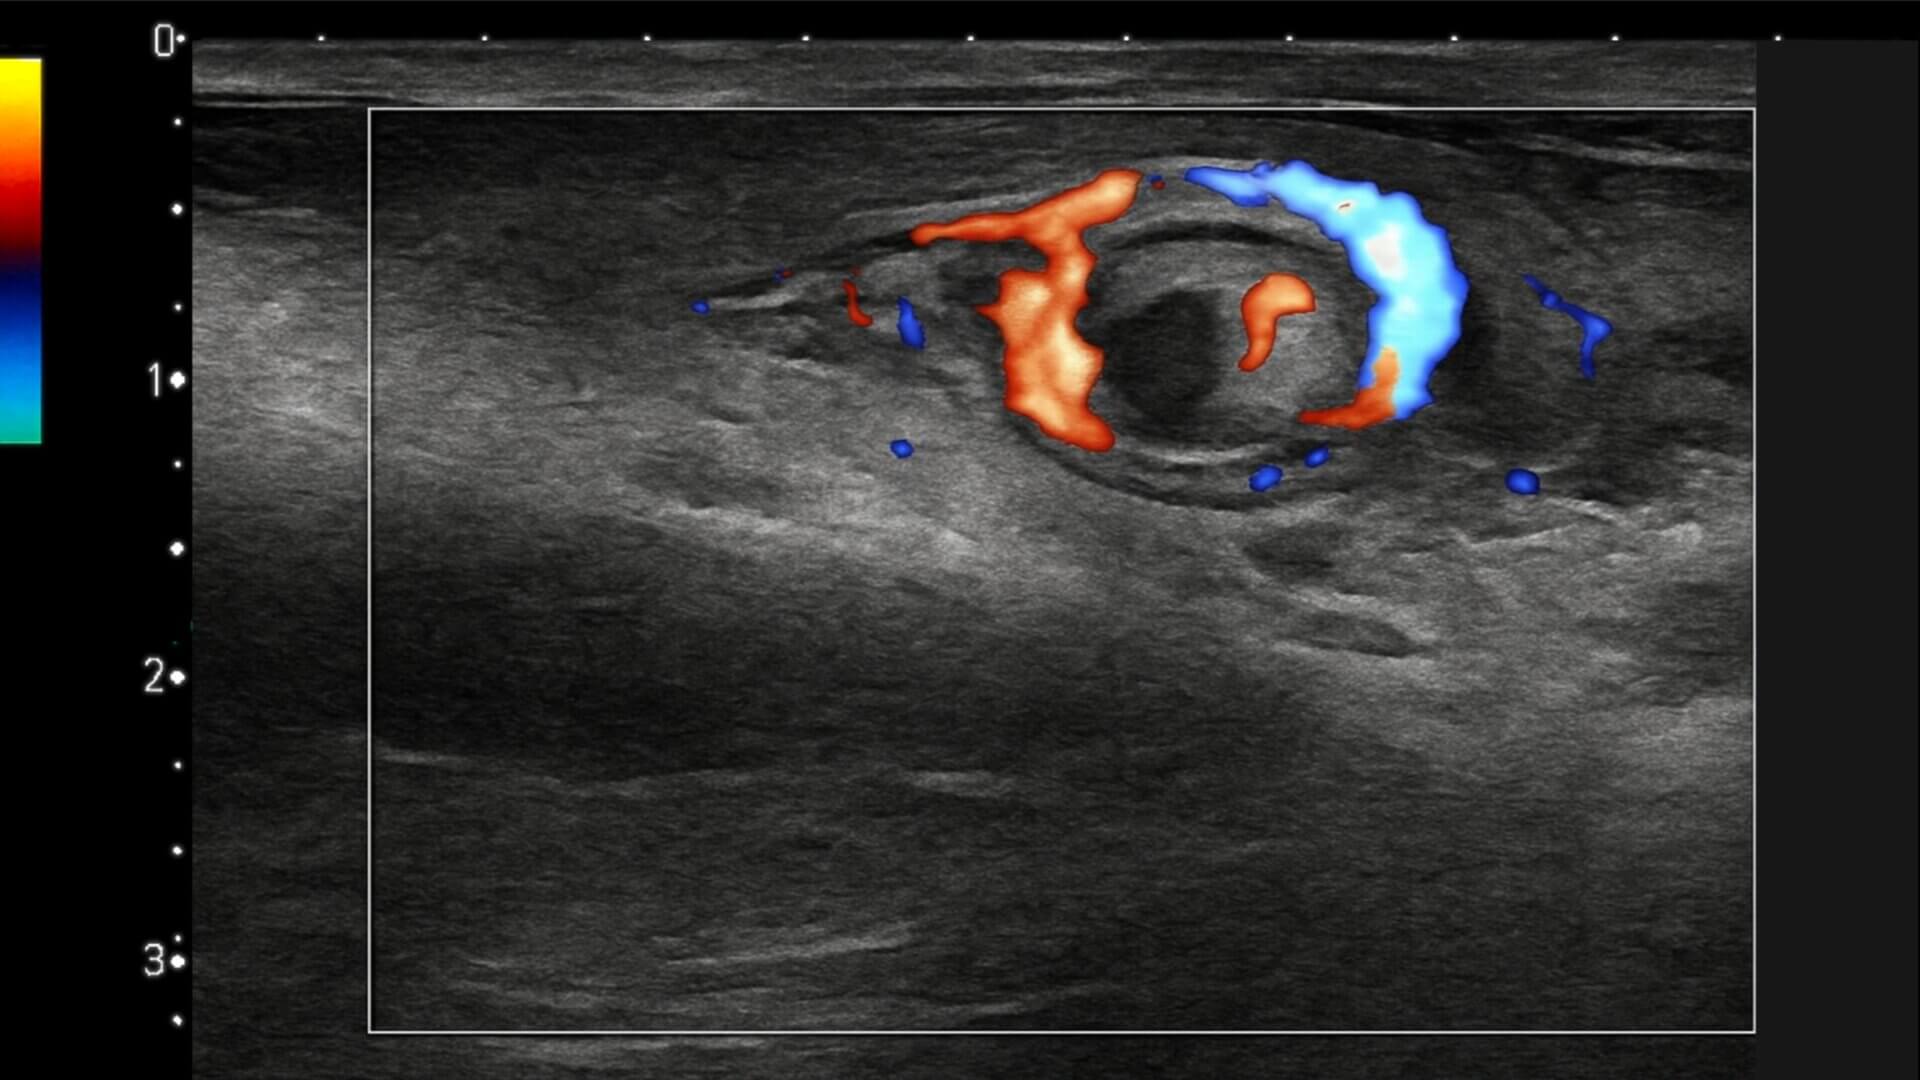

Das Whirlpool-Zeichen dese Samenstrangs ist ein direktes radiologisches Zeichen, das bei der sonographischen Diagnostik einer Hodentorsion auftritt. Es gilt als spezifischster und sensitivster Sonographiebefund zur Diagnose einer kompletten oder inkompletten Hodentorsion.

In der Sonographie zeigt sich eine spiralförmigen Verdrehung des Samenstrangs, die in der Farbduplex-Sonographie ein strudelförmiges Flussmuster aufweist.